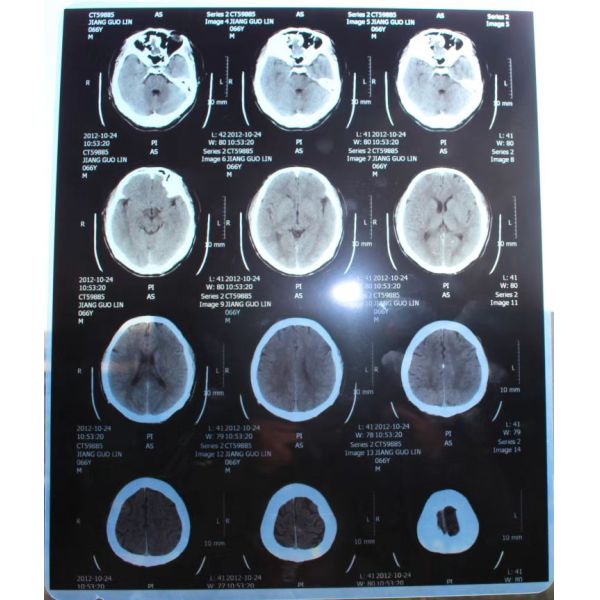

Application : For medical digital image output,like: CT,DR,MR,CR,etc.

Blue Laser Xray Film is a kind of conventional medical printing film suitable Fuji Xerox and OKI toner laser printer. This laser x-ray film use environmental PET materials to replace traditional silver sensitive film. With the characteristics of high speed, good definition, wide exposure latitude and great compatibility, it is widely used in hospital.

Blue laser x-ray film can be used for medical image output, like CT,DR,MR,CR, etc.